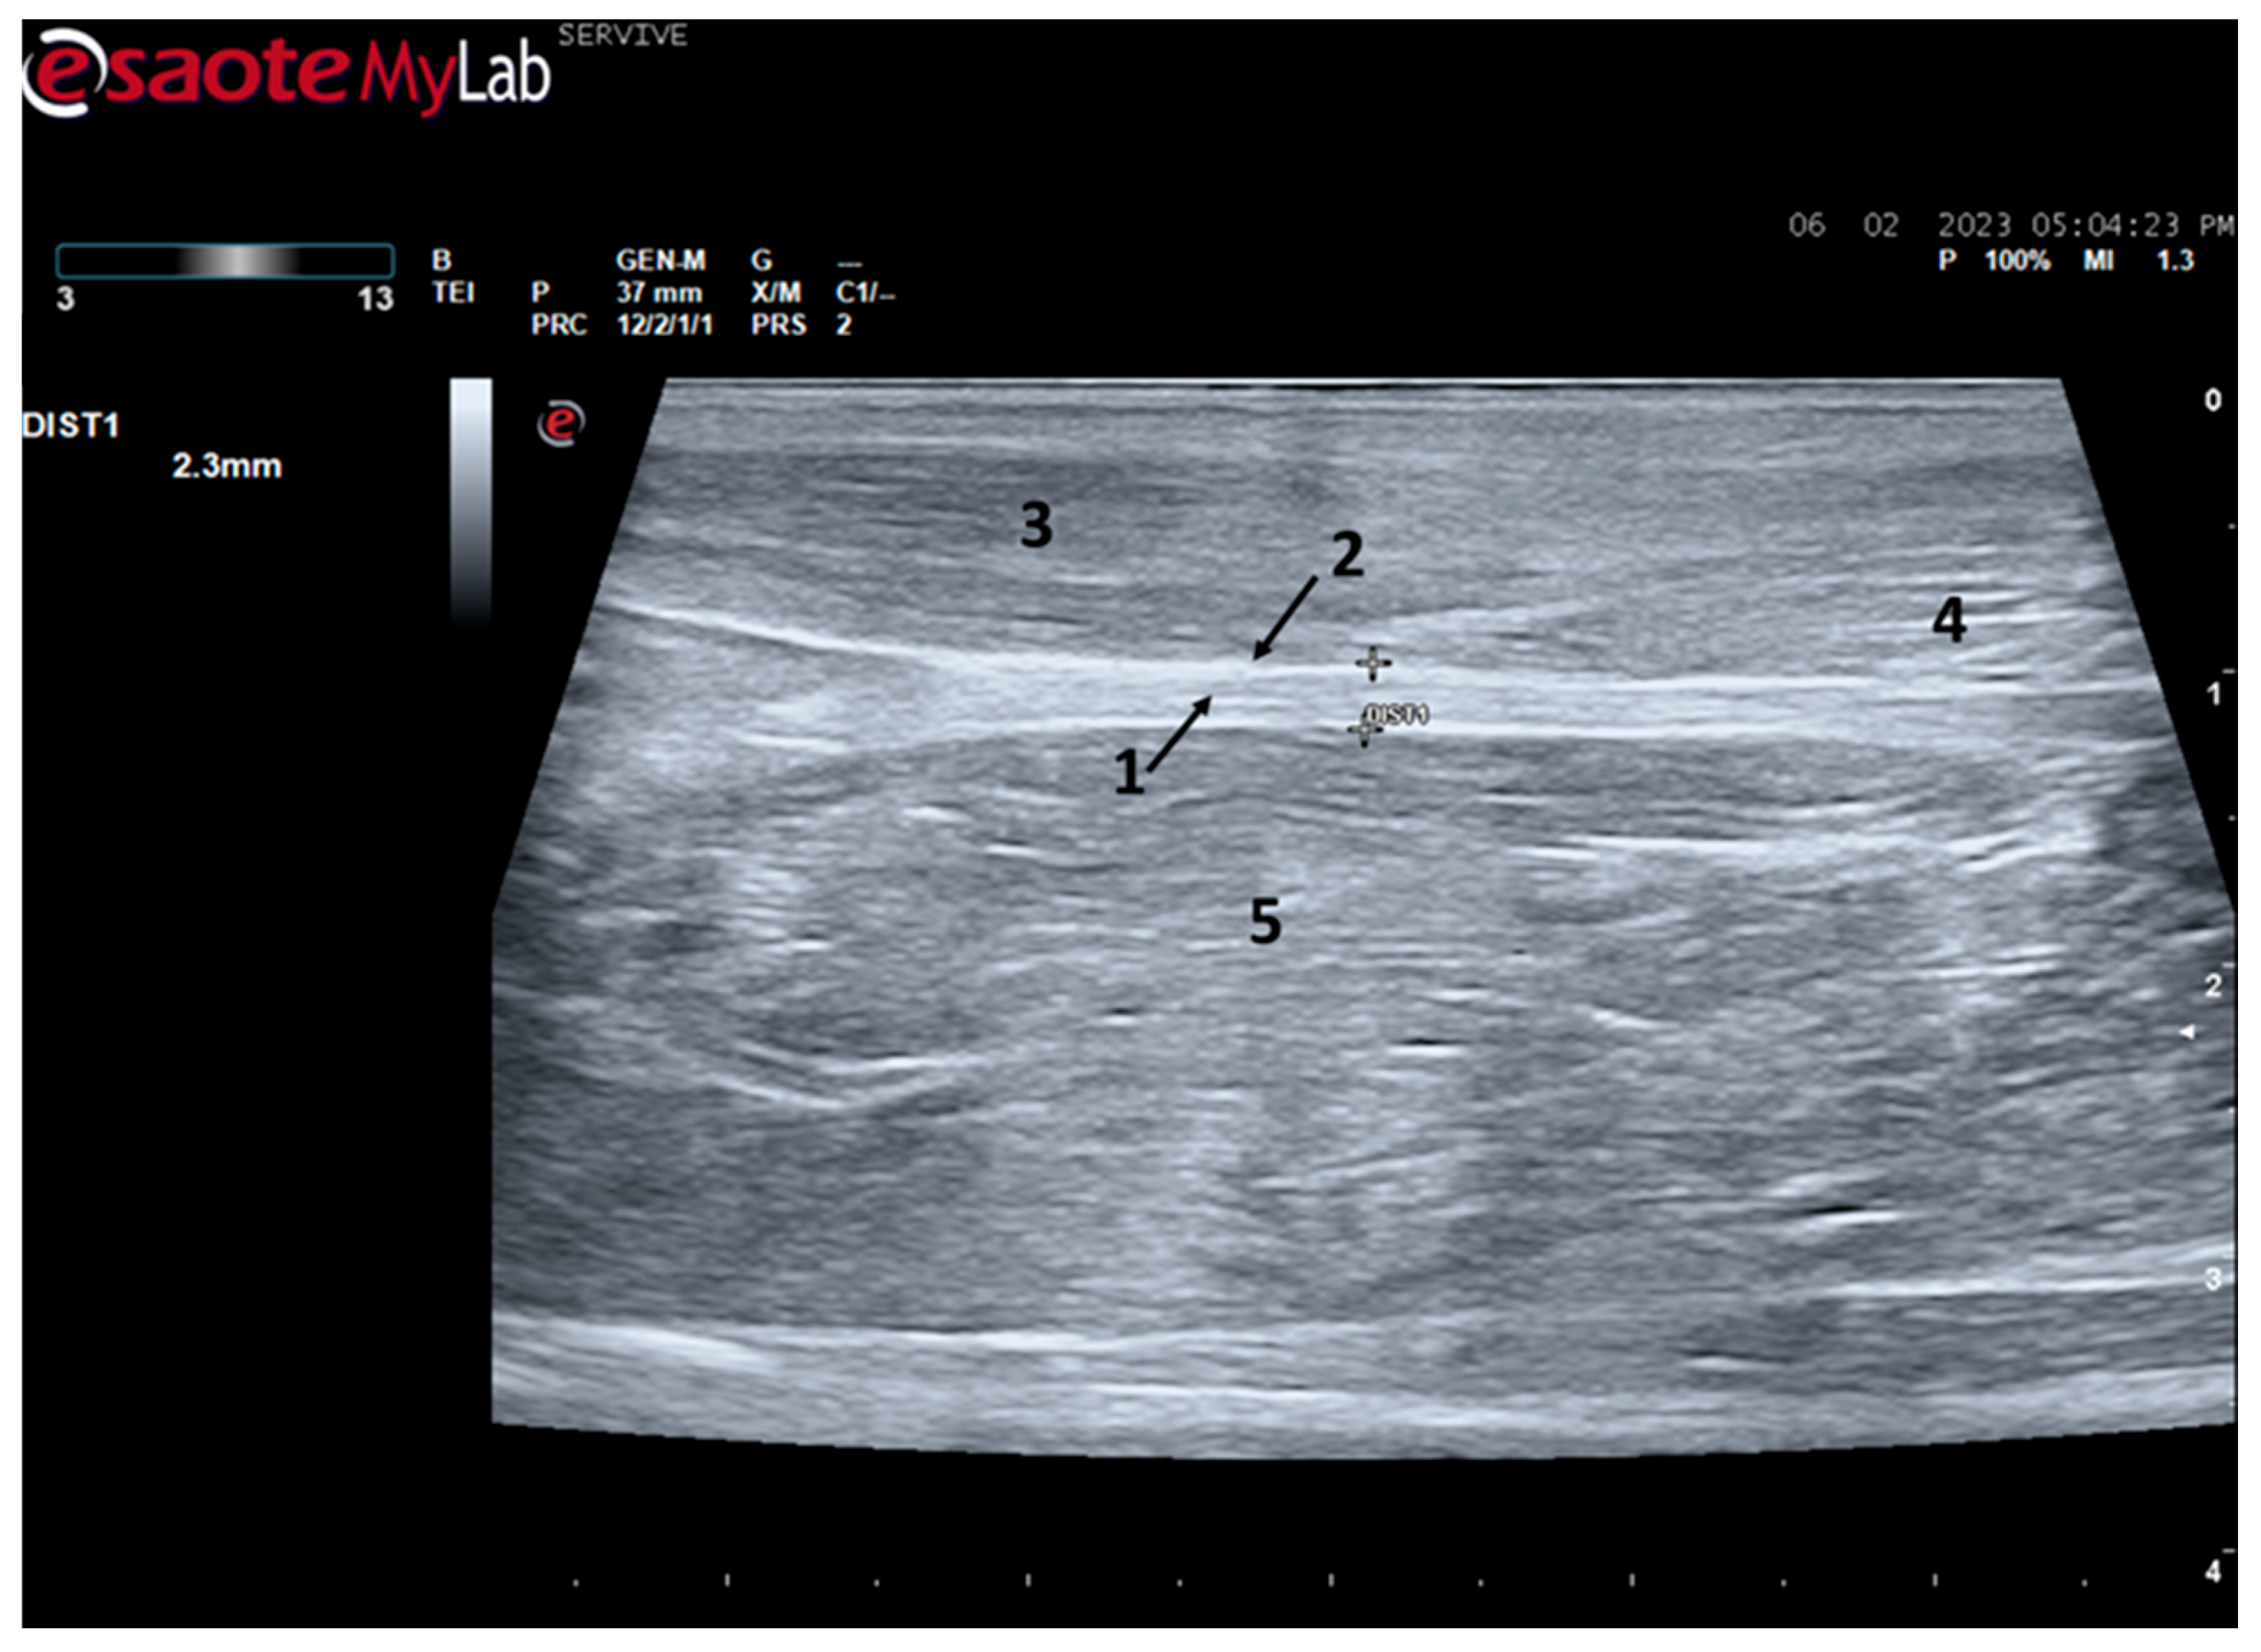

At the level of the greater ischiatic foramen, the sciatic nerve can be seen advancing between the dorsocaudal aspect of the acetabulum and cranial to the ischial tuberosity, passing over the muscle mass constituted by the gemelli and quadratus femoris muscles, close to the piriformis muscle and advancing caudally to the femur. The presence of these bony structures in the region, although they can be used as anatomical landmarks for nerve identification, can make a more proximal visualization difficult due to the curvature of the sciatic nerve and the hyperechogenicity of the bone that decreases contrast (Figure 3). Accompanying the nerve distally, it is visible between the muscles of the thigh, namely medially to the biceps femoris muscle, laterally to the adductor muscles, and caudally to the femur and the vastus lateralis muscle (Figure 4).

Figure 3.

Ultrasound image of the left sciatic nerve of a sheep after emergence from the greater sciatic foramen: (1) greater trochanter of the femur; (2) biceps femoris muscle; arrow—curvature of the sciatic nerve when passing between the reference bone structures. DIST1 represents the measurement of the diameter of the sciatic nerve.